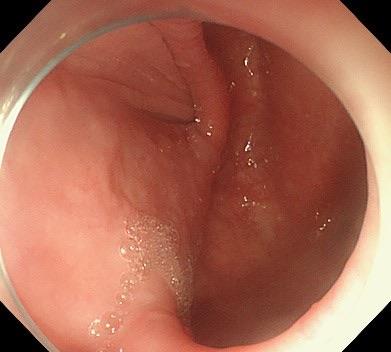

赵奶奶听了钟教授的病情解释后,恳请钟教授尽快手术。钟教授当天就安排赵奶奶住院检查,行术前评估,次日就给赵奶奶完成了内镜下微创手术:隧道内镜下食管憩室嵴切开术。钟教授运用内镜电刀在食管憩室上方建立“隧道”入口,打通“隧道”,在“隧道”内暴露出憩室嵴,最后应用内镜刀切开憩室嵴肌肉,在食管腔观察憩室嵴消失,金属夹关闭“隧道”入口。手术顺利,整个手术过程仅仅用时30分钟。术后复查造影,造影剂流出食管顺畅,不再潴留于食管憩室。赵奶奶术后经过禁食、胃肠减压、抑酸、营养支持等治疗,1天后进食流质饮食无明显不适,未再呕吐。术后逐步增加饮食,赵奶奶也未再呕吐,并且体重逐步增加,精神越来越好。就这样,困扰了赵奶奶好多年的呕吐,竟然这么快就治好了。

图2  食管憩室,术后憩室嵴消失,造影剂顺畅流出食管